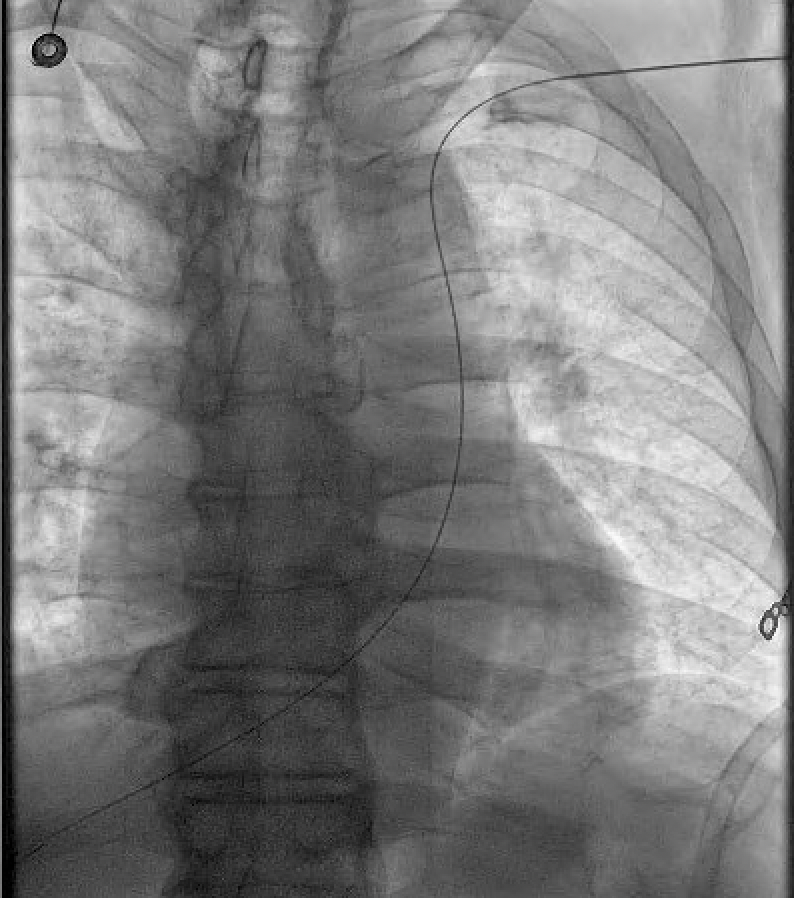

Cool case shared by my #EP colleague Dr. Hamid Afshar @BCMHeart During placement of CRT-D, he made a unique diagnosis present in 0.3% of general population!! Below is a still image of initial access. #ACCFIT, what's the diagnosis? #CardioTwitter #MedTwitter #EPeeps 1/4